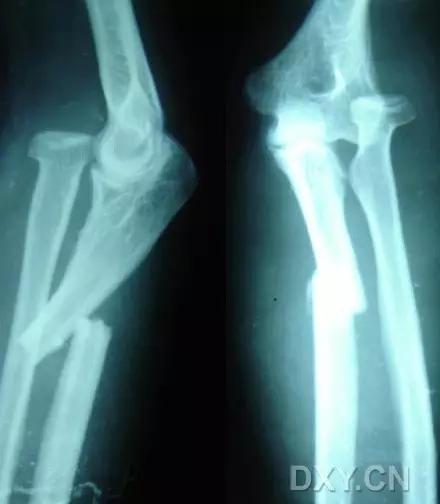

9. Monteggia 骨折(孟氏骨折)

尺骨近端 1/3 骨折合并桡骨头半脱位。

(来源:Radiopaedia)

成人 Monteggia 骨折

儿童 Monteggia 骨折